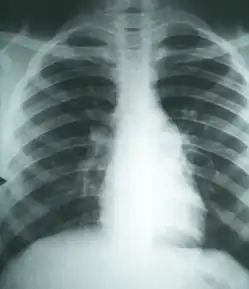

| Histopathological changes in a case of coccidioidomycosis of the lung showing a large fibrocaseous nodule. | |

Imaging

Chest X-rays rarely demonstrate nodules or cavities in the lungs, but these images commonly demonstrate lung opacification, pleural effusions, or enlargement of lymph nodes associated with the lungs.[4] Computed tomography scans of the chest are more sensitive than chest X-rays to detect these changes.[4]